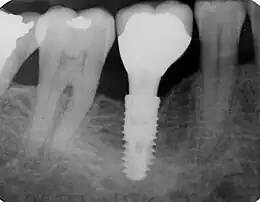

Un implant dentaire ou ancrage dentaire est un dispositif médical — sorte de vis en titane ou zircone ou polymère — inséré dans le maxillaire ou la mandibule et destiné à créer un ancrage capable de recevoir une prothèse dentaire amovible ou fixée[1].

Il existe différents types d'implants dentaires dont l'indication dépend des conditions osseuses du patient. La grande majorité des implants dentaires adoptent la forme d'une vis cylindro-conique dont l'état de surface est rendu rugueux après attaque acide et sablage. La connexion de la suprastructure prothétique est réalisée via un hexagone externe ou interne, ou encore un cône morse[4]. Ces implants sont insérés dans leur axe longitudinal, après forage d'un logement adapté en longueur et diamètre.

L’implant dentaire classique possède une forme de vis classique de 10 à 20 mm de longueur. C'est l'implant le plus répandu et le plus utilisé au monde. Ce type d'implant est à privilégier car il est le système le plus simple et le moins risqué. Toutefois il nécessite de bonnes conditions osseuses, c'est-à-dire un volume osseux suffisant. Une greffe osseuse peut être ajoutée en cas de manque d'os mais il vaut mieux ne pas ajouter un volume d'os trop important pour une meilleure durabilité et un traitement moins invasif.